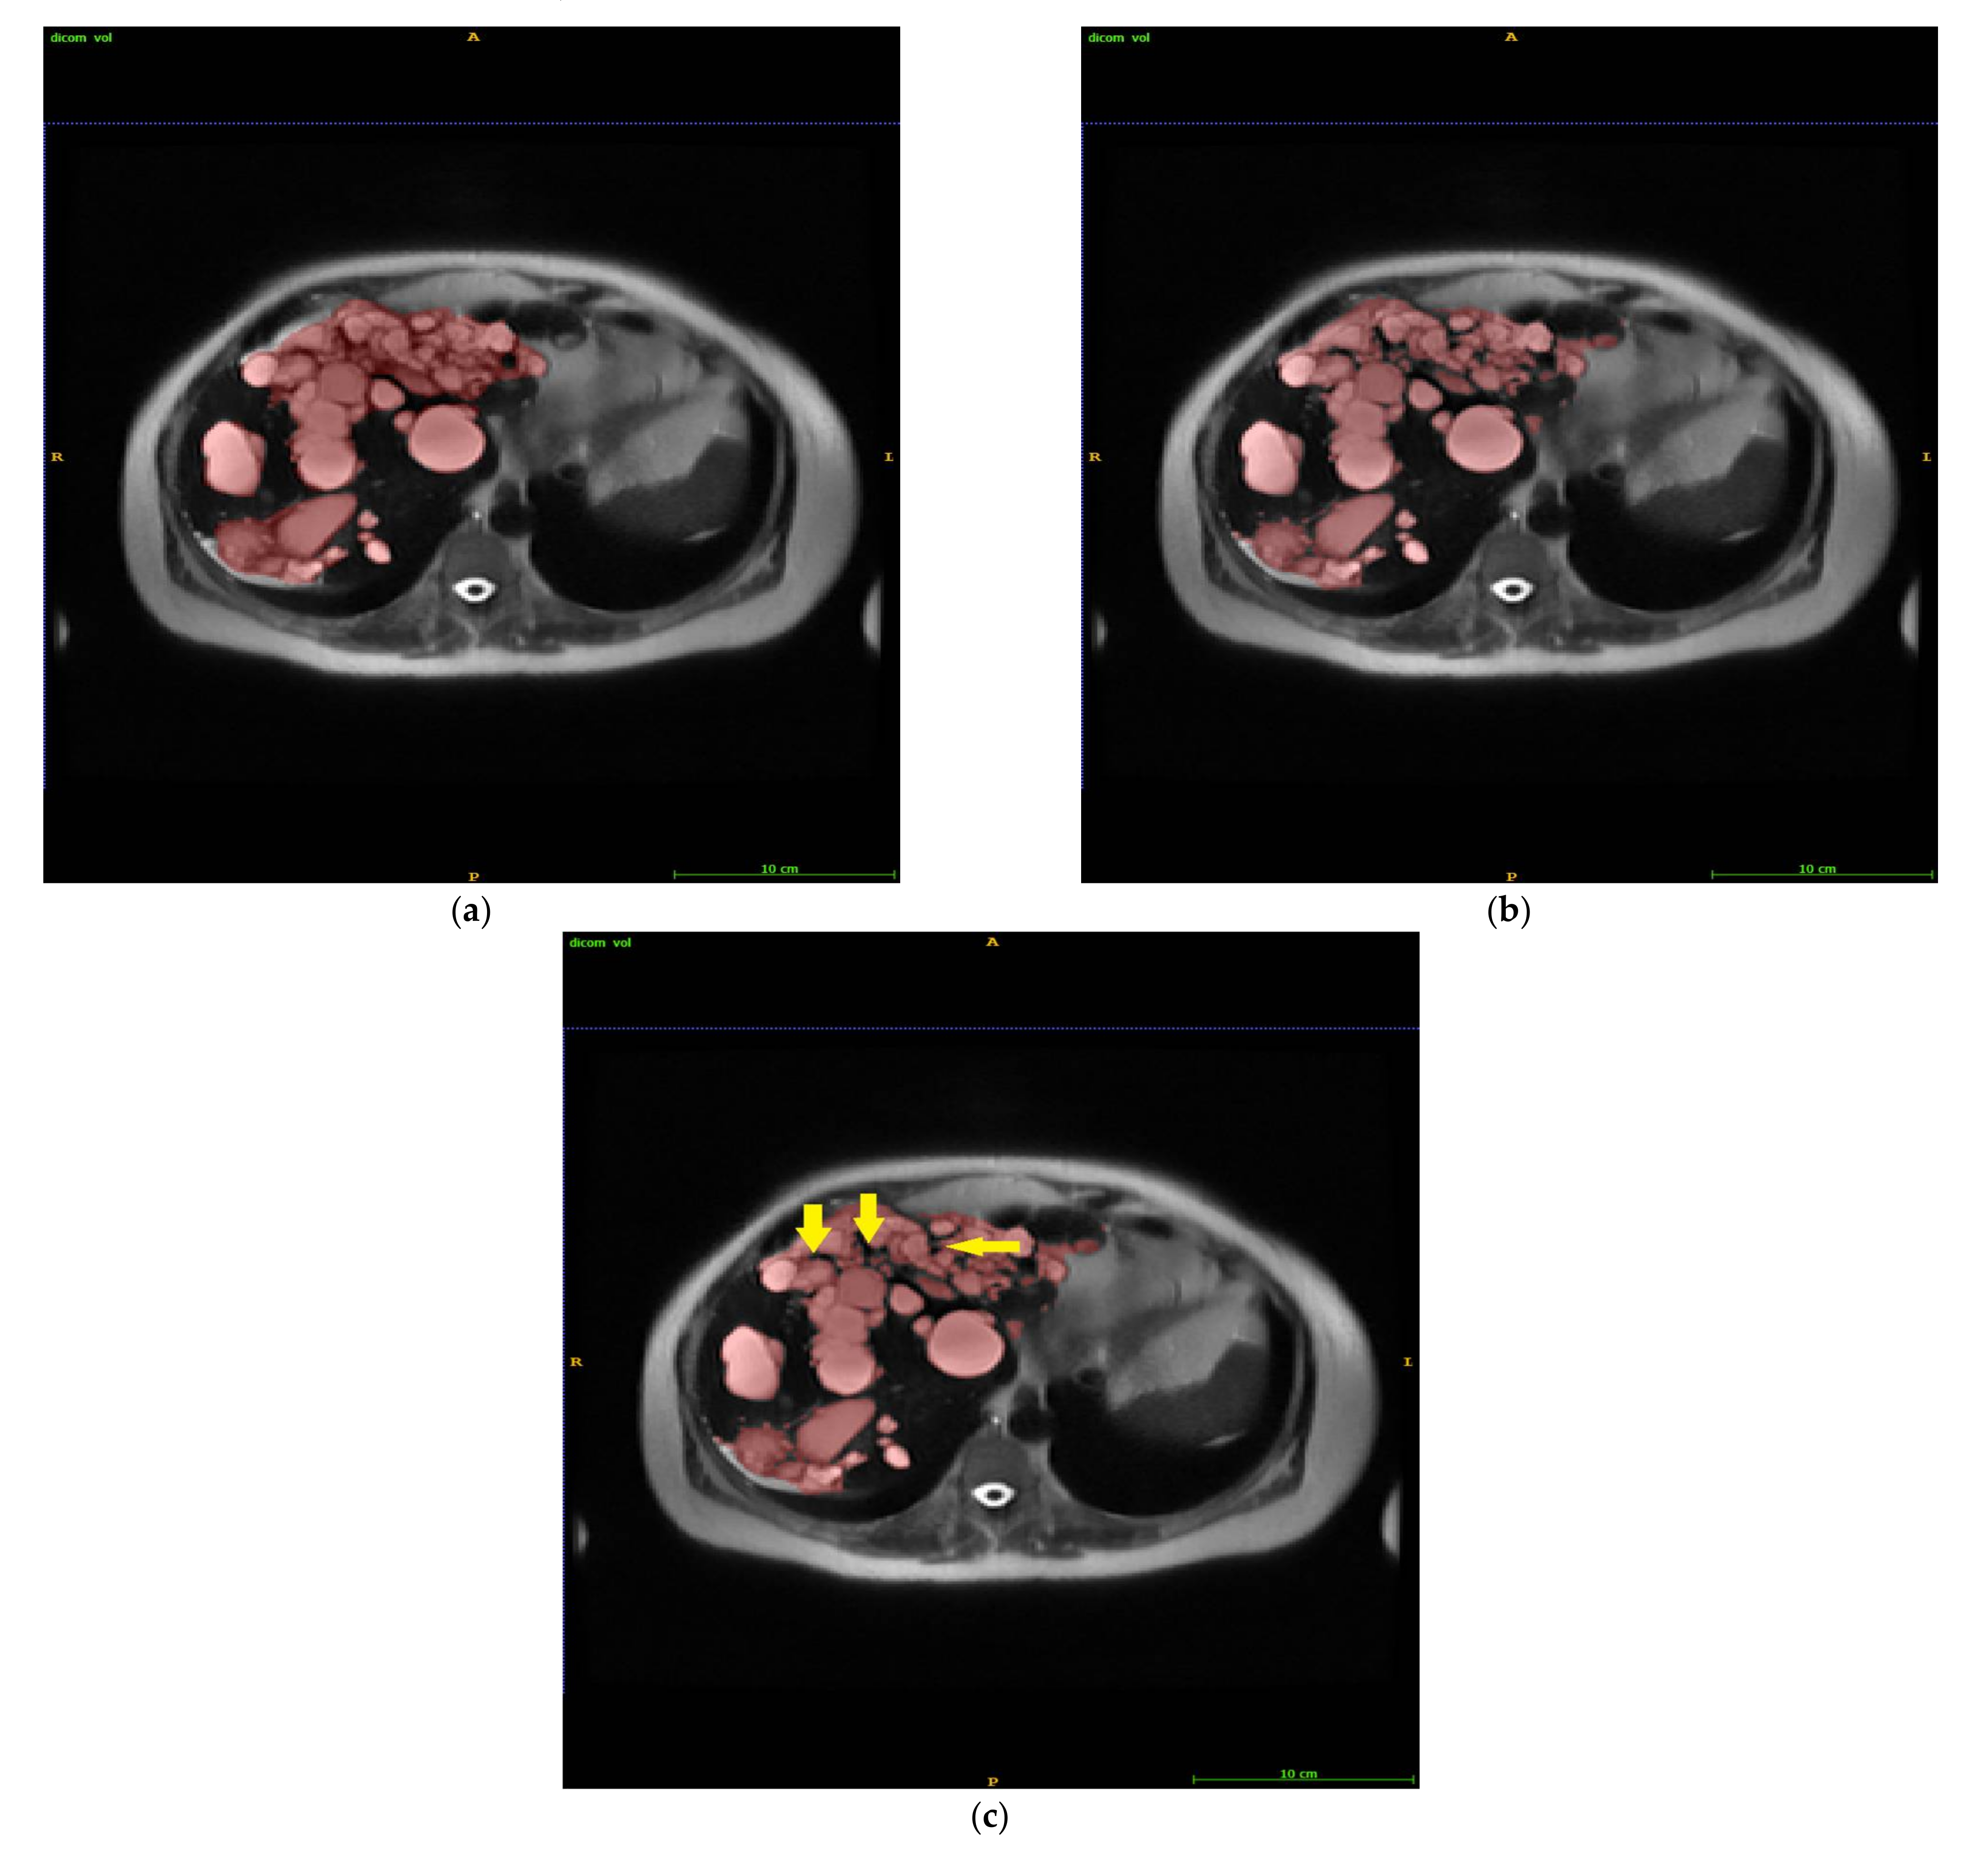

2.1. Intelligent Rapid Interactive Segmentation (IRIS) Method and Implementation